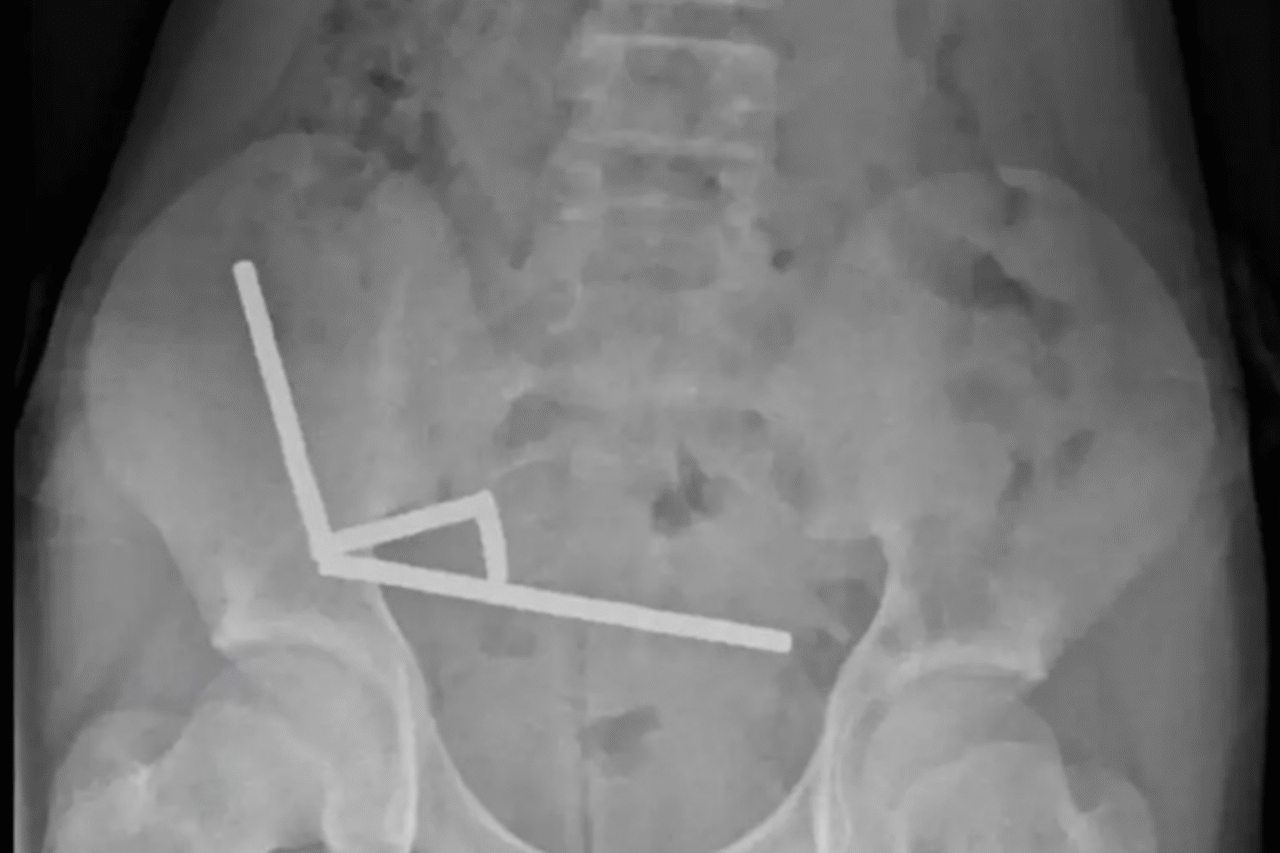

O jovem deu entrada no Hospital de Tauranga, na Ilha Norte, após quatro dias de fortes dores abdominais. Ele contou aos médicos ter ingerido entre 80 e 100 ímãs cerca de uma semana antes, mas exames revelaram quase o dobro do que imaginava. Radiografias mostraram quatro fileiras de ímãs presos em diferentes partes do intestino, atraindo-se mutuamente e comprimindo o tecido intestinal, o que acabou interrompendo o fluxo sanguíneo e provocando áreas de necrose.